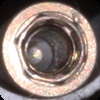

Stern EX

Connection Interface

External interface